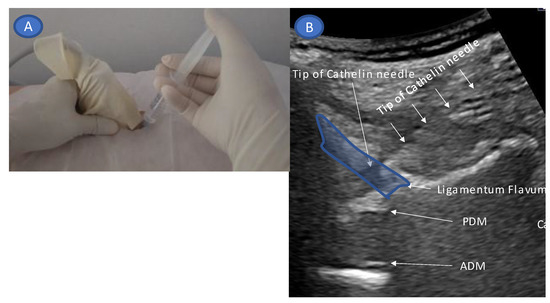

2. Technique Description

- Guide the needle into the ligamentum flavum.

- Advance the needle to the depth where resistance disappears (LOR).

- Confirm that the site of LOR is the epidural space.

- Confirm that the drug solution is appropriately distributed into the epidural space.

- Accurate needle tip guidance into the ligamentum flavum behind the epidural fat layer;

- Palpation of resistance by finger sense during ligamentum flavum insertion while confirming with sonography;

- Confirmation of the position of the needle tip in the ligamentum flavum;

- Tracing the spread of the drug in the epidural space using SMI during the injection.